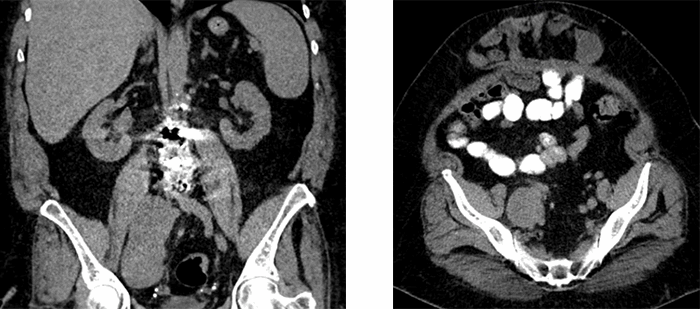

Unfortunately, the patient then developed progressively worsening abdominal distension and pelvic discomfort in 2018, and a repeat abdominal CT scan was obtained by the patient's primary care physician. The retroperitoneal mass remained stable in the year interim, however a slow growing neoplasm remained on the differential given the history of interval enlargement and weak pancytokeratin staining on histopathologic staining. Imaging findings were also remarkable for development of a large recurrent incisional hernia (Figure 1). Given the patient's pelvic pain presumed to be secondary to this persistent mass, in conjunction with her recurrent hernia, the patient was amenable to proceeding with abdominal wall hernia repair with concurrent resection of the right retroperitoneal mass.

Figure 1. Large right retroperitoneal mass (a) and associated large anterior wall abdominal hernia (b)